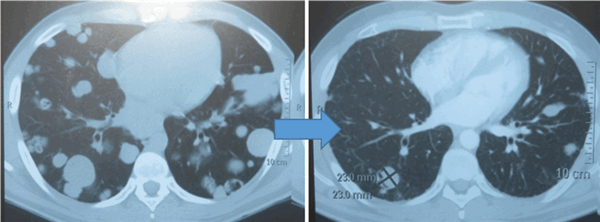

Химиотерапия

Показания к химиотерапии определяются степенью распространенности процесса, наличием легочных/внелегочных метастазов. Стандартным режимом химиотерапии при герминогенных опухолях является режим «BEP», включающий блеомицин, этопозид и цисплатин. Для пациентов с дыхательной недостаточностью, обширным поражением легких, во избежание легочной блеомициновой токсичности, как альтернативный вариант, может быть использованы режимы химиотерапии VIP (этопозид, ифосфамид, цисплатин) или ЕР (этопозид, цисплатин).

Для оценки эффективности химиотерапии каждые 2 цикла и после ее окончания проводится компьютерная томография исходных зон поражения, перед каждым циклом мониторинг уровня опухолевых маркеров. Рост маркеров на фоне лечения или после его завершения, а также замедление их снижения свидетельствует об активности опухолевого процесса и необходимости проведения второй линии химиотерапии.

![Метастазы в легких до лечения и после 4х циклов химиотерапии по схеме «ВЕР» (КТ грудной клетки)]()

Метастазы в легких до лечения и после 4х циклов химиотерапии по схеме «ВЕР» (КТ грудной клетки)